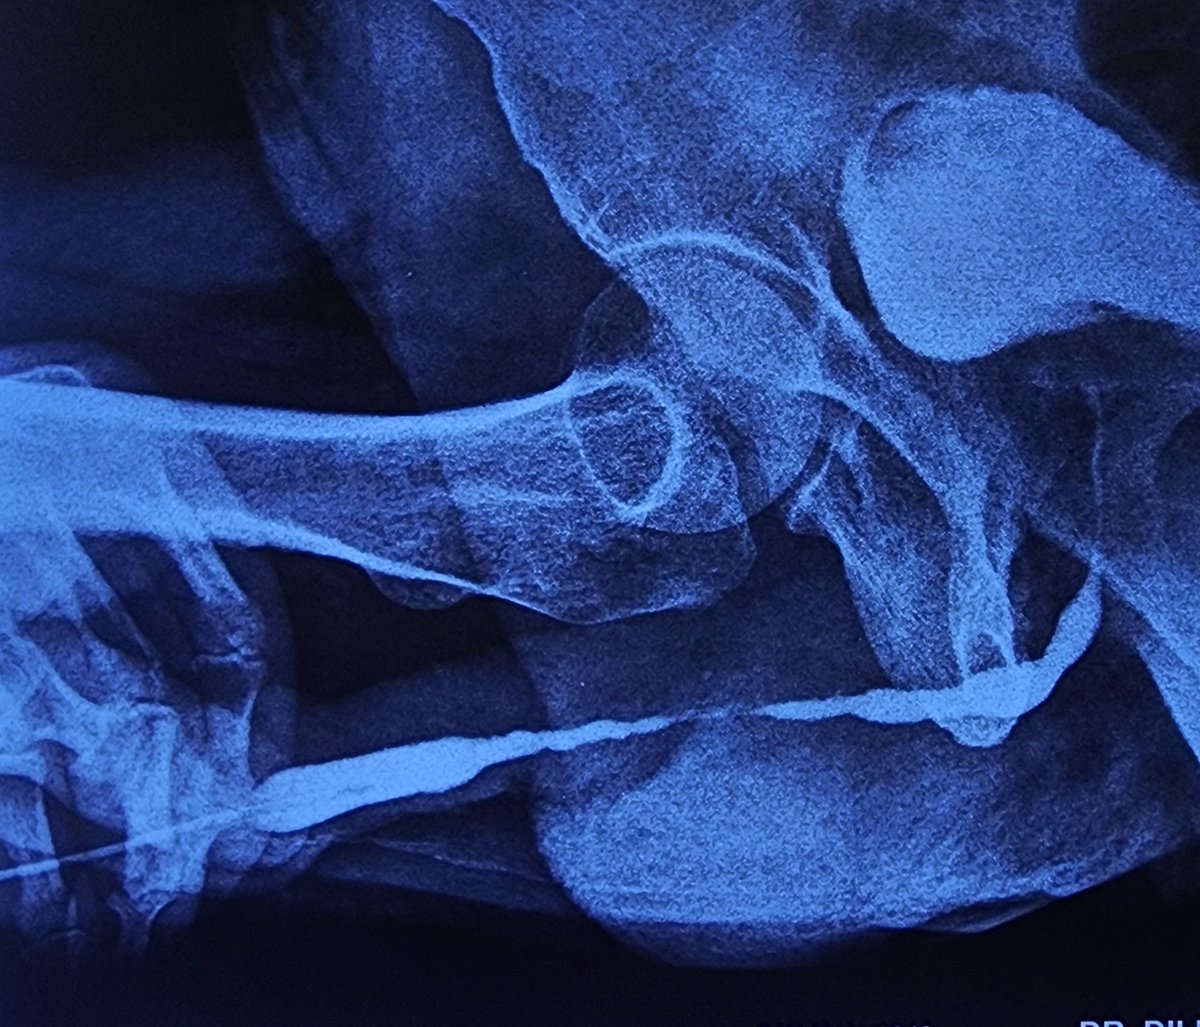

Inner Prepucial Graft Dorsal Onlay Urethroplasty for a long segment anterior Urethral stricture. @sanjaybkulkarni @drjoshi_pankaj